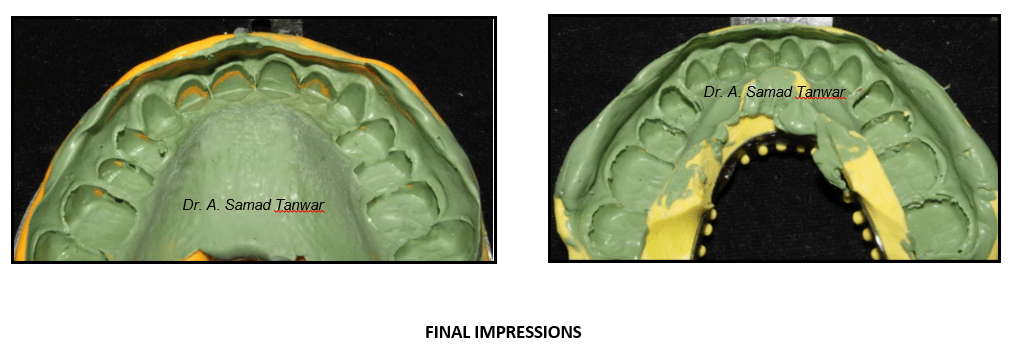

Double mix double step impressions were made using PVS elastomeric impression material

Double mix double step impressions were made using PVS elastomeric impression material